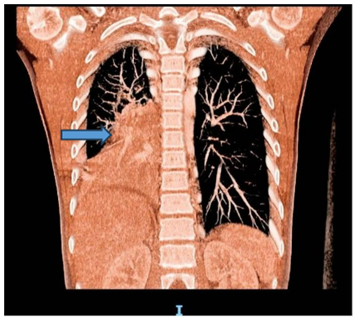

Following stabilization, flexible bronchoscopy revealed inflamed airways with a large obstructive clot in the right intermediate bronchus. As depicted in the Chest CT (Figure 1) demonstrated right lower lobe collapse with a "tree-in-bud" appearance, suggesting possible infection or hemorrhage. A CT angiogram raised suspicion of right lower lobe pulmonary sequestration (Figure 2).

Figure 2: CT angiography showing a doubtful right pulmonary lower lobe sequestration.